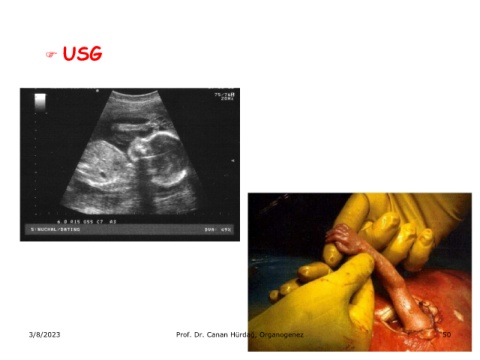

 USG